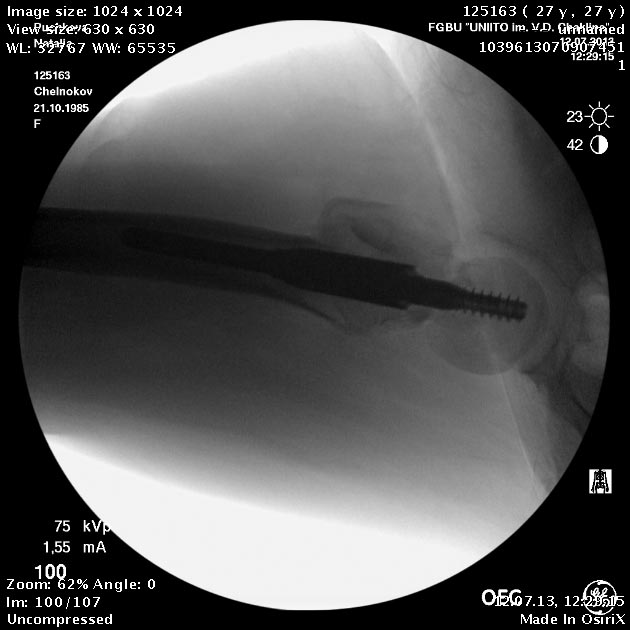

Пациентка приехала на этой неделе. Сегодня сделали правое бедро. Удалили винты, сделали чрескожную вальгизирующую остеотомию, зафиксировали Affixus. Второе бедро будем делать недели через 2.

Добрый день! Коллеги! Складывается впечатление, что вальгизация выполнена на уровне перелома шейки бедренной кости, а не в межвертельной зоне, непонятна возможность компресси в зоне перелома (винты позиционированы резьбовой частью в зоне перелома). и уж совсем не понятно статическое блокирование дистальной части штифта. С уважением Ушаков С.

Головка до и во время остеотомии была диафиксирована несколькими спицами, так что положение ее не менялось. На картинке подрисован диафиз, был он примерно там. Дистальный винт введен больше на всякий случай, чтобы дистальный конец гвоздя не болтался. А большой винт проходит через периферический отломок, так что введение динамического винта внизу ничего не дало бы.

Добрый день! неплохо было бы еще медиализировать диафиз. а проксимальный винт вероятнее всего попал в зону остеотомии, уж больно тесно.